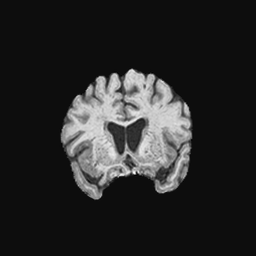

Exp. 1: Segmented adult brain data is used to evaluate our network’s regression performance with known ground truth Tisubscript𝑇𝑖T_{i}. 85 brains from the ADNI data set[1] were randomly selected; 70 brains for ΩtrainsubscriptΩ𝑡𝑟𝑎𝑖𝑛\Omega_{train} and 15 brains for ΩvalidationsubscriptΩ𝑣𝑎𝑙𝑖𝑑𝑎𝑡𝑖𝑜𝑛\Omega_{validation}. Fig. 2 shows an example slice of the ground truth and the reconstructed ΩΩ\Omega.

Figure 2: Example slice from the segmented adult brain MRI data set (a); reconstruction from 300 ωisubscript𝜔𝑖\omega_{i} based on SVRNet regression without SVR (b); SVR initialised with SVRNet predictions after eight iterations of SVR (c). Note that SVRNet (b) predicts individual slice transformations only from image intensities without any initial world co-ordinates of the sampled slice. (d) shows the achieved PSNR in dB when comparing the volumes of (b) and (c) to (a).

Reconstructing from Ti^^subscript𝑇𝑖\hat{T_{i}} initialisation without SVR yields a PSNR of 23.7 ±plus-or-minus\pm 1.09; with subsequent SVR the PSNR increases to 29.5±plus-or-minus\pm2.43 when tested on 15 randomly selected test volumes after four iterations of SVR.